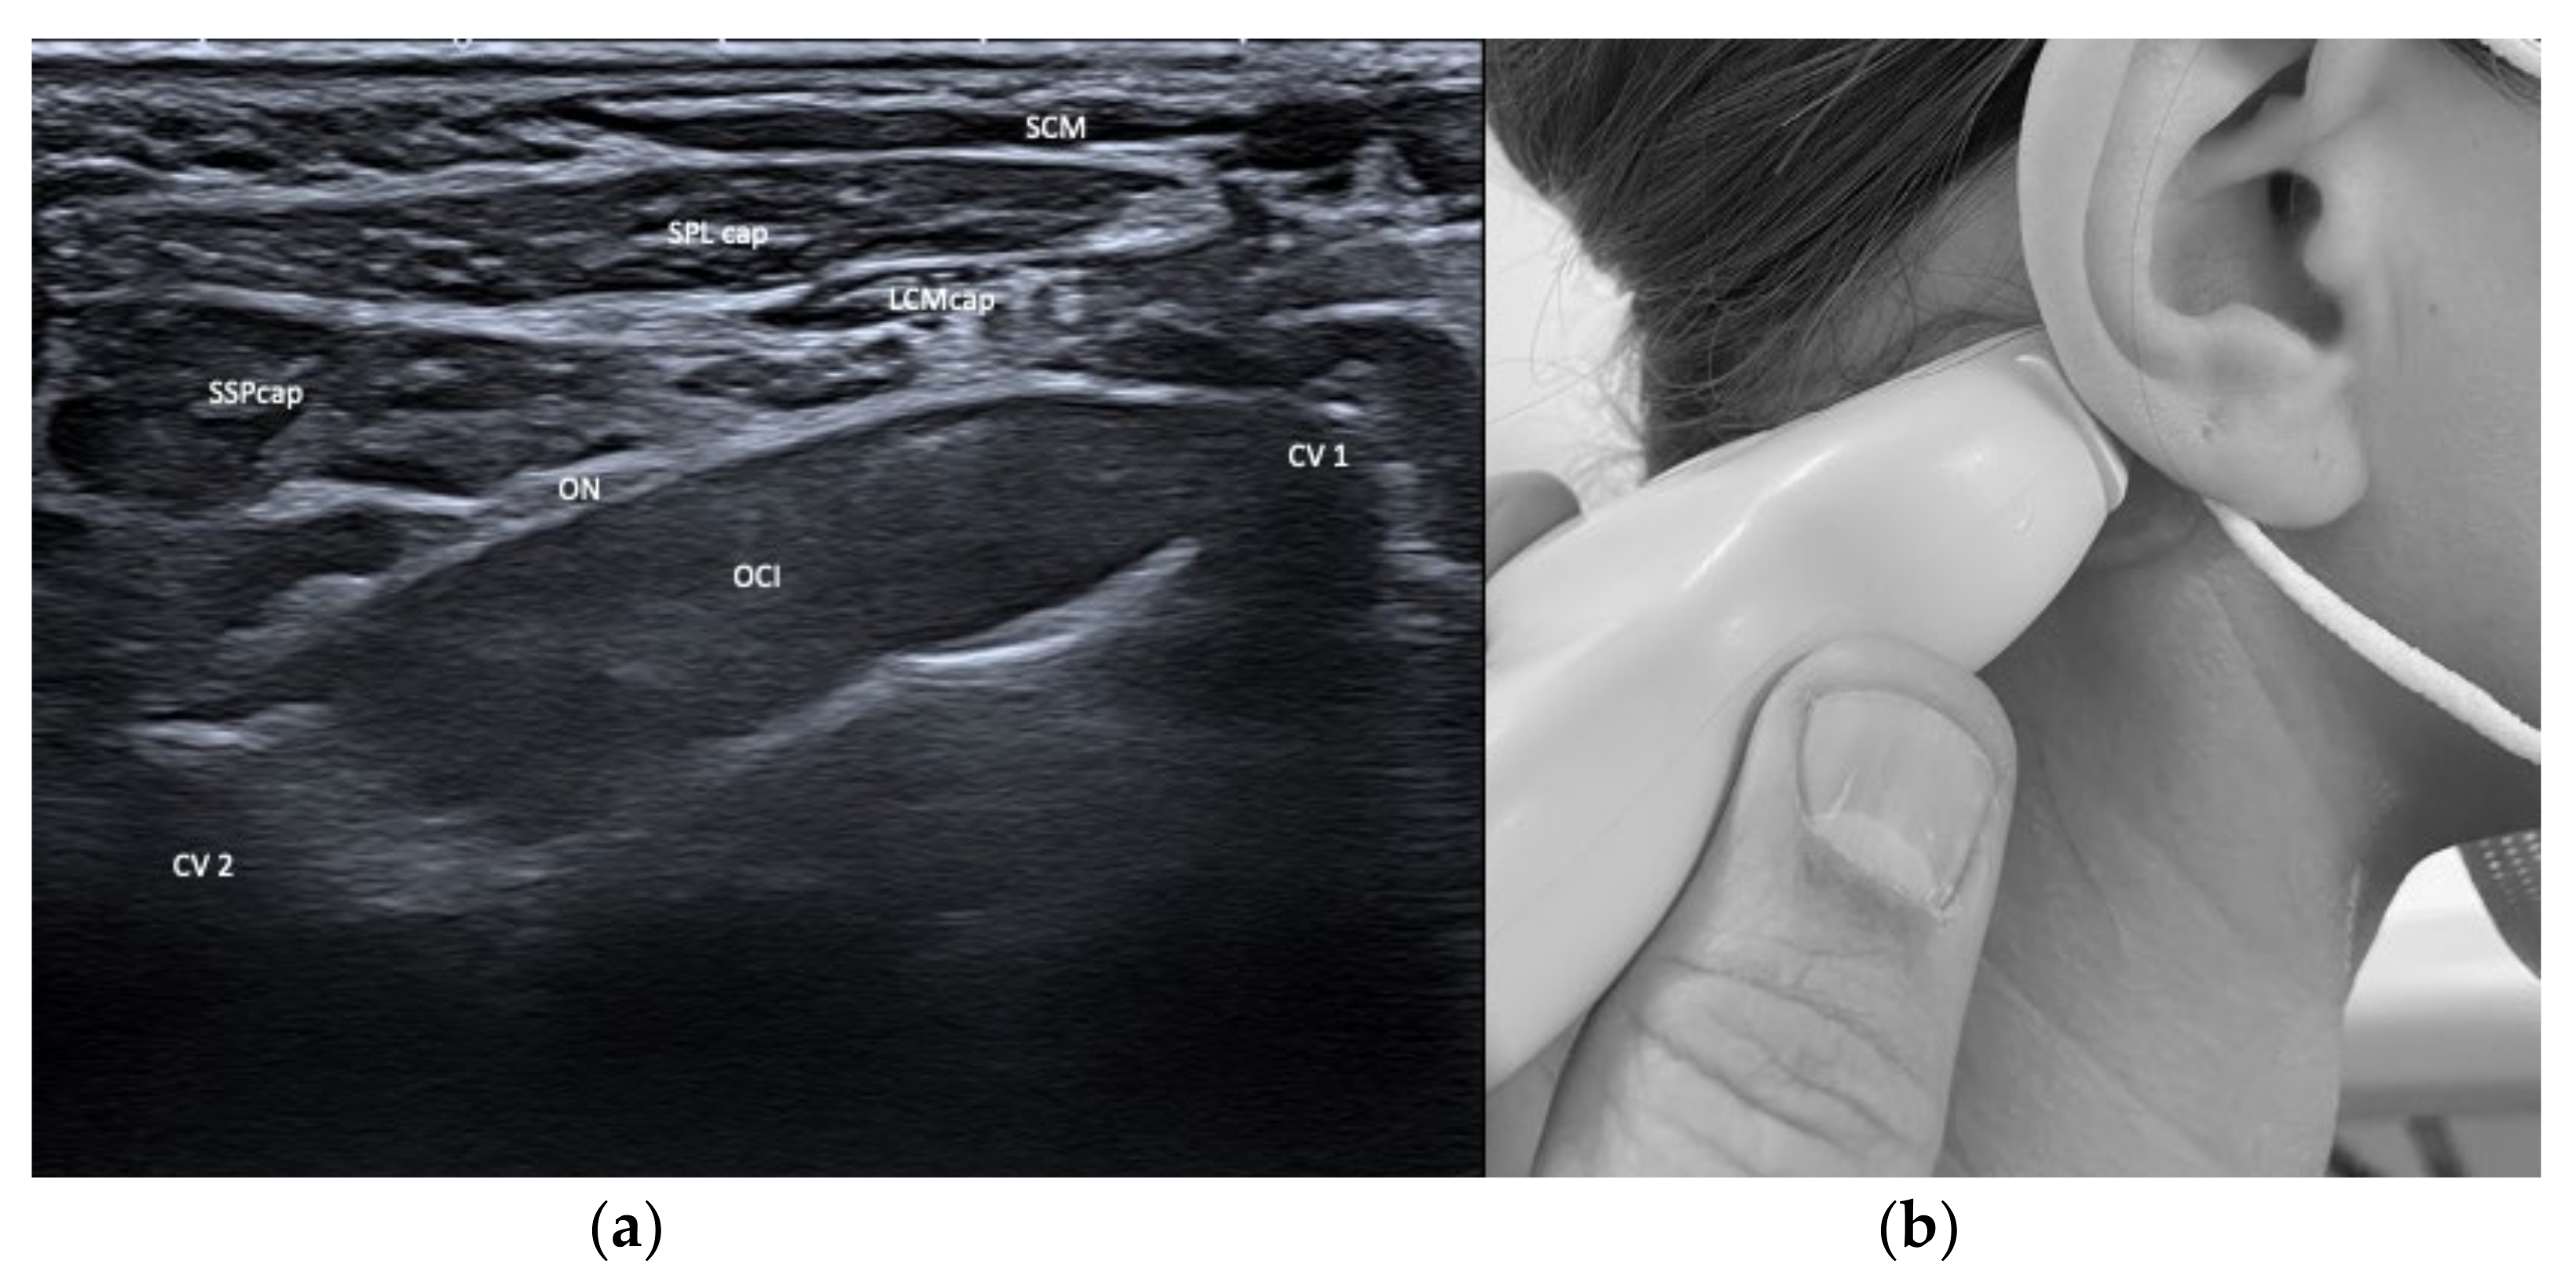

| Obliquus capitis inferior (OCI) | Ipsiversion of head | +++ | +++ | SSPcap, RCM, vertebral artery, greater occipital nerve | Adjacent muscles are all extensors of the head |

| Rectus capitis major (RCM) | Extension of head | +++ | +++ | SSPcap, OCI | |

| Semispinalis capitis (SSPcap) | Extension of head | + | + | SPLcap, OCI | Strongest extensor muscle of head and neck |

| Splenius capitis (SPLcap) | Ipsiversion of head | ++ | ++ | major occipital nerve, SPLcap/cer, LSMcap, OCI | Prominent reduction in bulk from repeated injections possible |